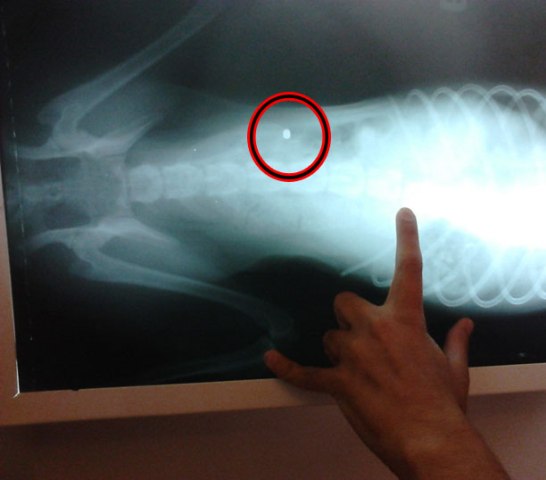

Άλλο ένα θύμα απάνθρωπης επίθεσης σε ζώα στην περιοχή της μονής του Ταξιάρχη στο Μανταμάδο της Λέσβου είναι ο Ερμής, ένα σκυλάκι μόλις πέντε μηνών που κάποιος «άνθρωπος» σφήνωσε στη σπονδυλική του στήλη μία σφαίρα, αφήνοντάς το ανάπηρο και τώρα θα πρέπει να φύγει τόσο μικρό από τη ζωή, καθώς θα υποστεί ευθανασία.

Όπως αναφέρει το lesvosnews.gr, η κτηνίατρος που περιθάλπει το άτυχο τετράποδο είναι υποχρεωμένη να κάνει ευθανασία στον Ερμή, αφού δεν θα μπορέσει με τίποτα να ορθοποδήσει και μόνο πόνο θα νιώθει σε όλη του τη ζωή.

Ο Ερμής σύμφωνα με την κτηνίατρο πριν πυροβοληθεί είχε κακοποιηθεί βάναυσα αφού είχε σημάδια από χτυπήματα σε όλο του σχεδόν το σώμα.